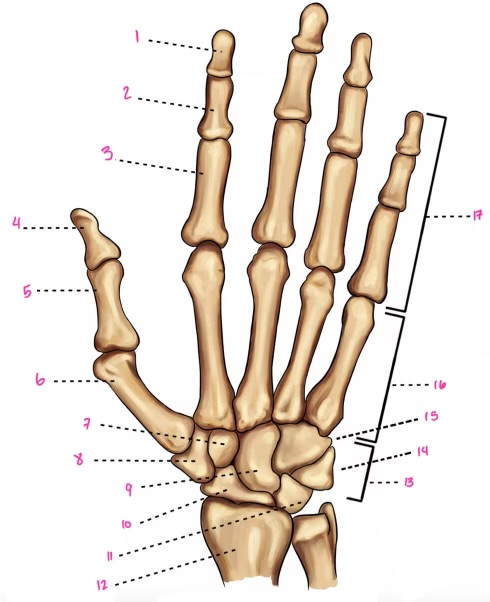

1

1

2

2

3

3

4

9

5

10

6

11

7

14

8

15

9

16

10

17

11

18

12

1

13

2

14

3

15

4

16

5

17

6

18

7

19

8

20

9

7

22

8

23

9

24

10

25

11

26

13

27

14

28

15

29

16

30

17

Phalanxes